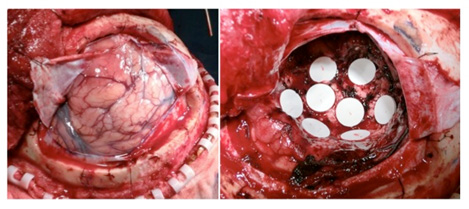

ギリアデル留置したグリオーマ手術症例

左前頭葉グリオーマに対して、左前頭葉開頭し、硬膜切開し展開(左)。

腫瘍全摘した後、腫瘍摘出腔にギリアデル8個を留置(右)。この後、手術野専用の綿を載せ、フィブリン糊で固定して閉創する。